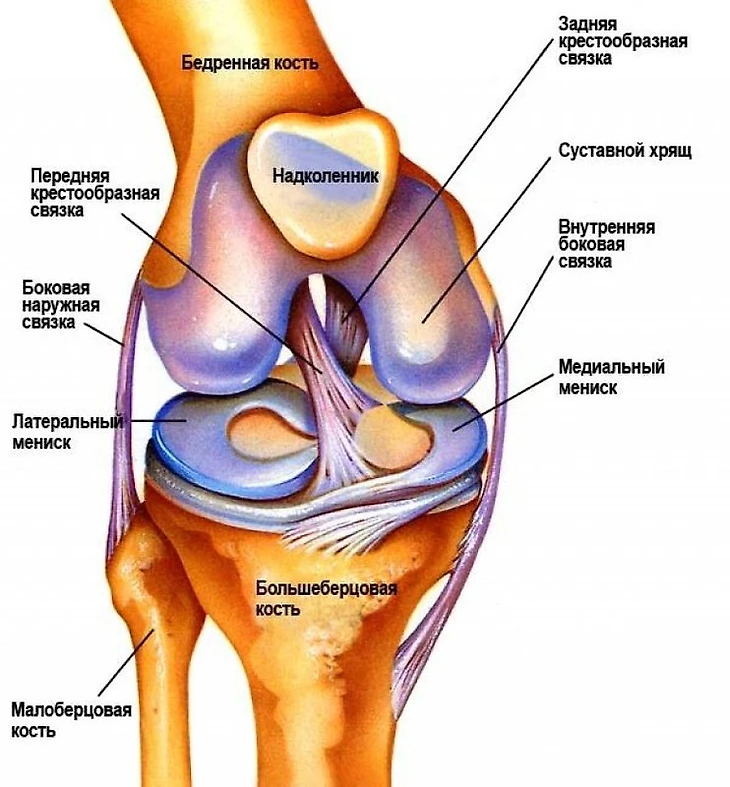

Разрыв крестообразных связок в футболе считается одной из самых страшных травм. Ключевыс фактором опасности ее возникновения считается то, что получить ее можно в любой момент даже по случайности - в 70% случаев ничто заранее не предполагает подобного разрыва, обычный неудачный стык или неправильно выставленная опорная нога запросто может привести к подобной травме.

Добавляет драматизма и долгий срок реабилитации - коленные связки заживают минимум полгода, а последующие месяцы восстановления прежней работоспособности в усиленном темпе лишь усугубляют состояние мышечной ткани вокруг поврежденной связки, что зачастую провоцирует возникновение новых травм, в этот раз мышечных. Тем более разрыв связки сигнализирует о том, что суставы и связки игрока подвержены подобным травмам, то есть велика вероятность рецидива или разрыва другой связки после продолжительного восстановления. В 20% случаев, зафиксированных в профессиональном футболе за последние 15 лет, травма возвращалась вновь.

Крестообразные связки отвечают за всю работу колена, они стабилизируют коленный сустав и не позволяют голени смещаться в стороны. Помимо прочего, на их работе строится и распределение мышечного давления при ходьбе и беге - степень напряженности мышц напрямую зависит от состояния крестообразных связок. Учитывая динамику задействования связок при движении колена, для ее разрыва достаточно одного сильного контакта в определенном месте - вроде удара, что приведет к смещению голени в противоположную от давления сторону и порвет связку. Помимо прямого контакта, даже обычное смещение голени в момент приземления после прыжка или неудачного падения способствует развороту головки кости в другом направлении, что также приведет к разрыву скрепляющей связки.